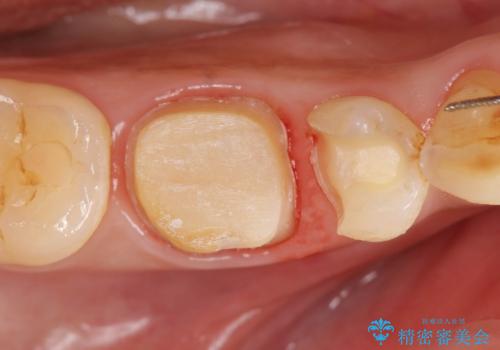

治療途中の歯 セラミック治療を希望され来院

- 治療途中で数ヶ月放置してしまった歯のセラミック治療を希望され来院されました。

セラミッククラウン・セラミックインレーを用いた精密治療を計画します。